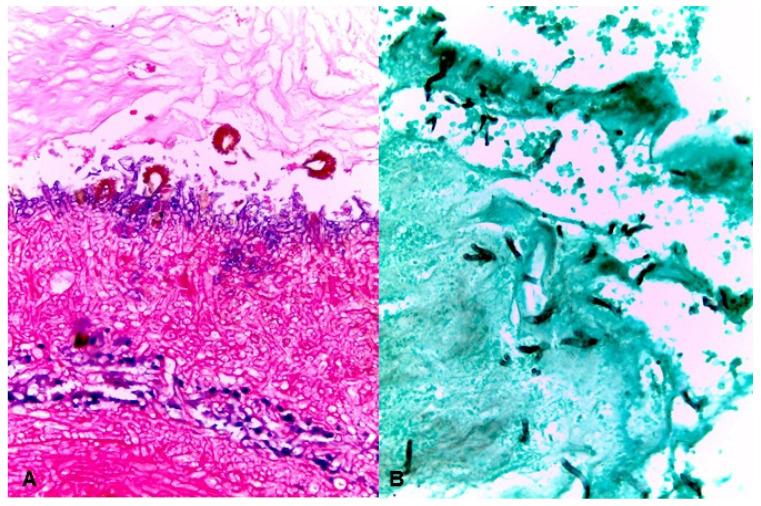

Aspergillosis and mucormycosis are filamentous fungal infections occurring predominantly in immunocompromised patients. Fulminant process with rapid infiltration of the contiguous tissue is distinctive for both type of fungi. The rhinocerebral co-infection by and Mucorales is very rare and is usually associated in immunocompromised patients with a high mortality rate. This rare co-infection leads to difficulties in diagnosis, and therapeutic delays can result in a poor prognosis. Overall, the treatment of choice is surgical debridement and liposomal amphotericin B. This paper describes a combined aspergillosis and mucormycosis case in a diabetes mellitus type 2 patient with chronic ulcerations of the palatal and cheek. To our knowledge, this is the first report of an uncommon co-infection of and in a rhino-orbital presentation.

曲霉病和毛霉病是主要发生在免疫功能低下患者中的丝状真菌感染。这两种真菌的显著特征是病程凶险,会迅速浸润相邻组织。曲霉和毛霉目真菌的鼻脑合并感染非常罕见,通常发生在免疫功能低下的患者中,死亡率很高。这种罕见的合并感染导致诊断困难,治疗延迟会导致预后不良。总体而言,首选的治疗方法是手术清创和脂质体两性霉素B。本文描述了一名2型糖尿病患者腭部和颊部慢性溃疡合并曲霉病和毛霉病的病例。据我们所知,这是首例关于曲霉和毛霉罕见合并感染导致鼻眶病变的报告。